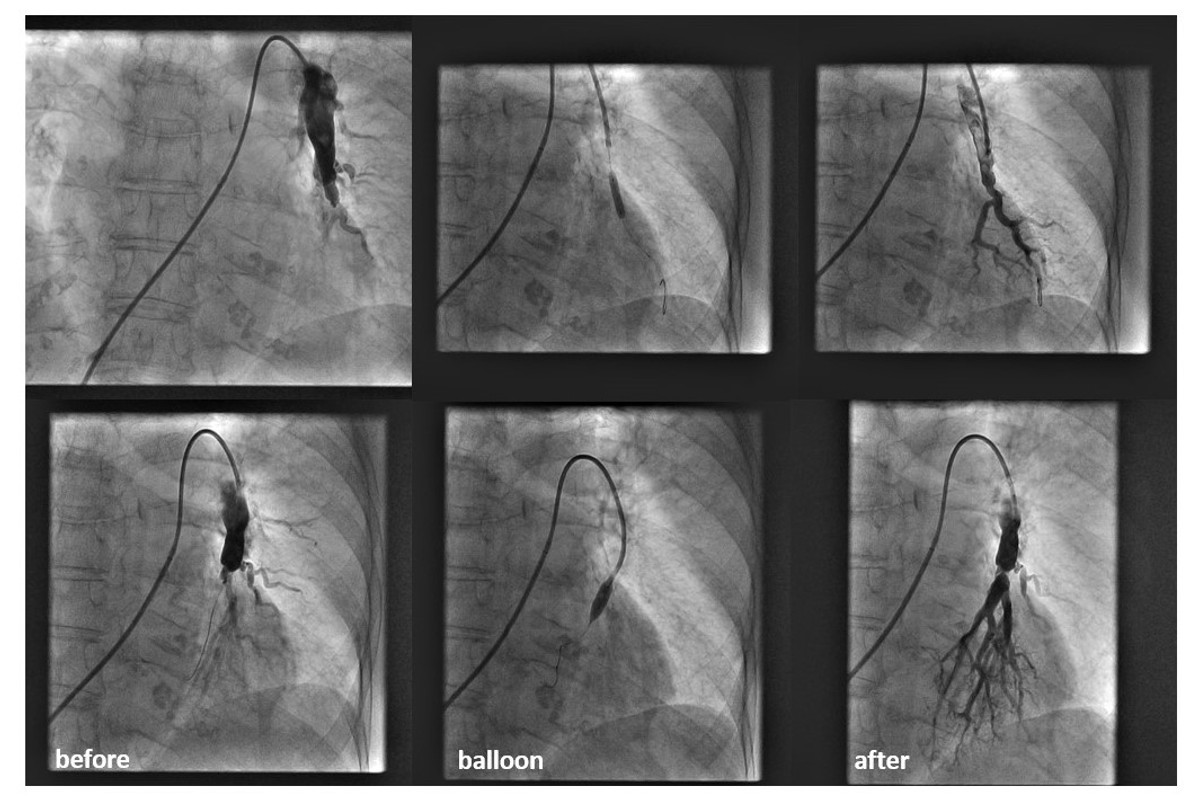

Prva balonska angiplastika plućnih arterija u CTEPH bolesnika u Hrvatskoj izvedena je u Kliničkom bolničkom centru Split u dva bolesnika. Riječ je o minimalno invazivnom endovaskularnom intervencijskom tretmanu kojim se otvaraju trombozirane, sužene pa čak i zatvorene plućne arterije. Do sada su svi bolesnici u Republici Hrvatskoj bili slani na BPA intervencije u specijaliziranu kliniku u Austriji preko Referentnog centra Ministarstva zdravstva za bolesti plućne cirkulacije pri KBC Zagreb, no zahvaljujući splitskim kardiolozima to više nema potrebe.

Za sve je zaslužan tim interventnih kardiologa: dr. sc. Mislav Lozo uz asistenciju dr. sc. Dina Mirića te medicinskih sestara Kristine Ruščić, Mirjane Lativnović i Katarine Gavranić kao i inženjera radiologije Josipa Ujevića i Matee Bolčić, a sve uz proktorstvo prof. Slobodana Obradovića interventnog kardiologa sa VMA iz Beograda koji ima bogato iskustvo od oko 200 učinjenih procedura. Zahvati su protekli bez komplikacija, a oba bolesnika su već par sati nakon učinjene BPA kazali da su 'napokon prodisali'.